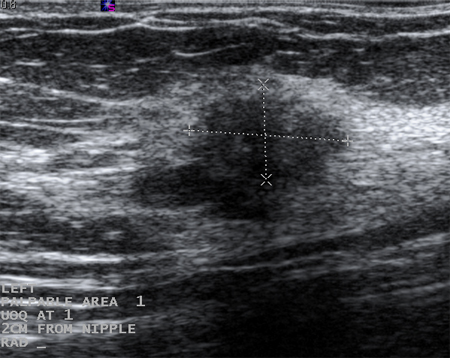

Imagen en ultrasonografía de un carcinoma invasivo

Cortesía del Dr. Lane Roland, University of Louisville; utilizada con autorización